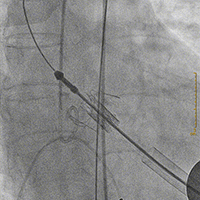

将装置好J-Valve23mm主动脉瓣的输送鞘送至主动脉瓣瓣环平面,释放定位装置并造影定位

稳定释放瓣膜